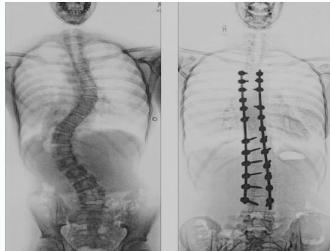

Surgical Treatment

Indications:

- Curves >40° in skeletally immature patients

- Progressive curves

Procedure:

- Correction

- Instrumentation

- Fusion

Surgery

- Adult documented progressive curves